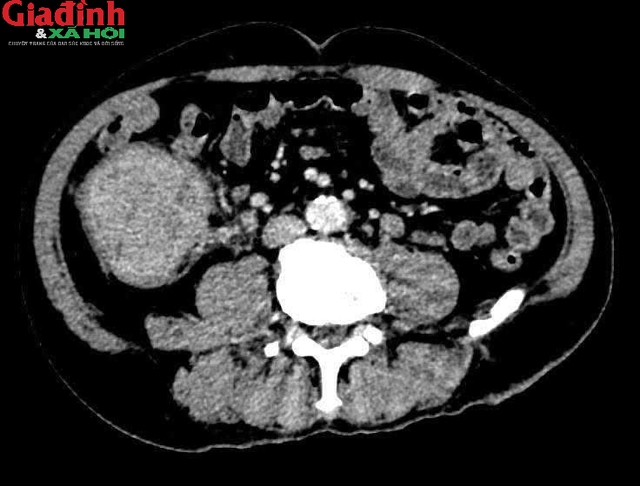

Bệnh nhân T.X.T (73 tuổi) có tiền sử tăng huyết áp, đái tháo đường type II, di chứng liệt nửa người sau tai biến mạch máu não và viêm gan B. Sau khi thăm khám bằng các phương pháp cận lâm sàng như chụp CT, MRI và nội soi dạ dày – đại tràng, các bác sĩ Bệnh viện 19-8 xác định người bệnh bị ung thư đại tràng phải đã di căn sang gan trái.

Các bác sĩ xác định người bệnh bị ung thư đại tràng phải đã di căn sang gan trái.

Sau khi hội chẩn, các bác sĩ đã lựa chọn phương án phẫu thuật đồng thời hai tổn thương trong cùng một lần can thiệp, bao gồm cắt bỏ khối u đại tràng phải và cắt thùy gan trái có tổn thương di căn.